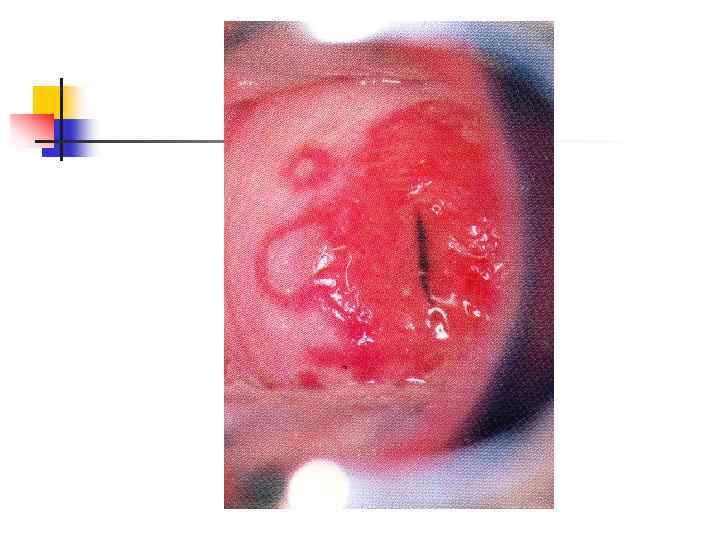

Герпес: первичная инфекция-герпетический стоматит Множественные очень болезненные эрозии на слизистой нижней губы. Десны гиперемированы и отечны - на них и на зубах видны отложения фибрина (из -за боли зубы не чистили несколько дней). У больного лихорадка; поднижнечелестные лимфоузлы увеличены и болезненны при пальпации.

Герпес: первичная инфекция-герпетический стоматит Множественные очень болезненные эрозии на слизистой нижней губы. Десны гиперемированы и отечны - на них и на зубах видны отложения фибрина (из -за боли зубы не чистили несколько дней). У больного лихорадка; поднижнечелестные лимфоузлы увеличены и болезненны при пальпации.